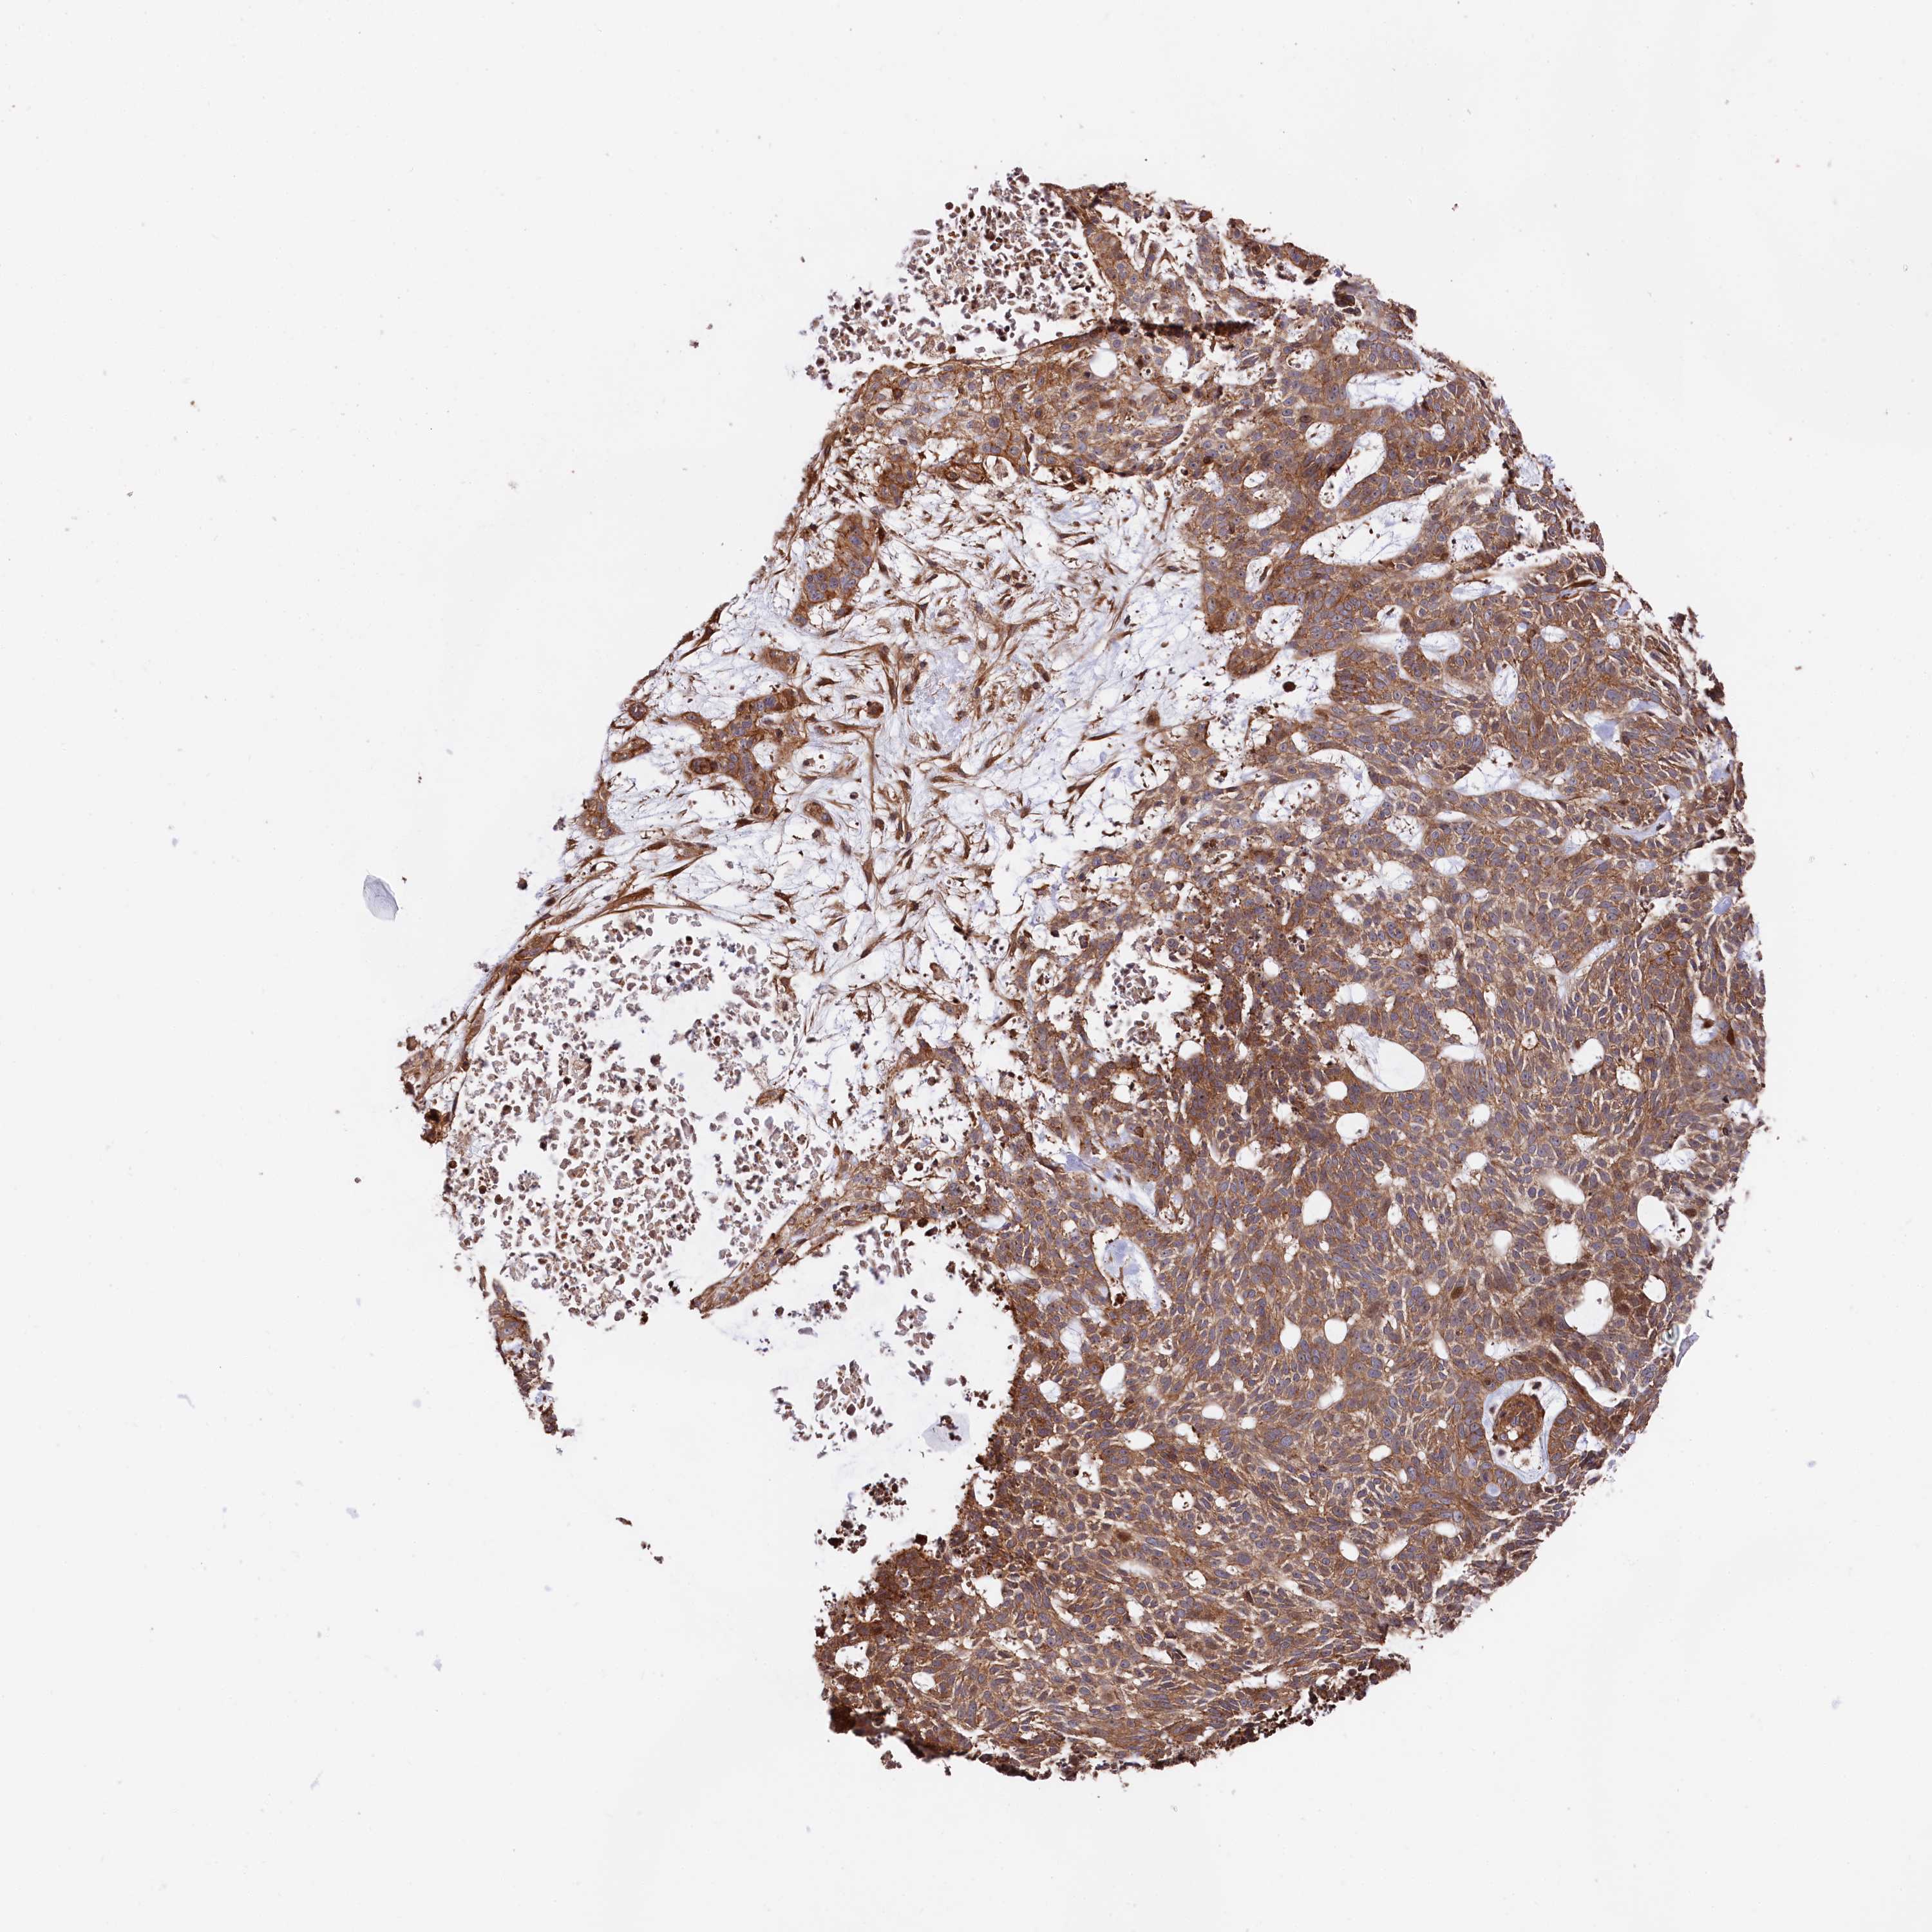

SKIN CANCER - Protein expressioni

A mouse-over function shows sample information and annotation data. Click on an image to view it in a full screen mode. Samples can be filtered based on level of antibody staining by selecting one or several of the following categories: high, medium, low and not detected. The assay and annotation is described here.

Antibody stainingi

Antibody staining in the annotated cell types in the current human tissue is reported as not detected, low, medium, or high, based on conventional immunohistochemistry profiling in selected tissues. This score is based on the combination of the staining intensity and fraction of stained cells.

Each image is clickable and will lead to virtual microscopy that enables deeper exploration of all samples and also displays staining intensity scores, fraction scores and subcellular localization as well as patient and tissue information for each sample.

Antibody HPA037929

Antibody HPA037930

Staining

High

Medium

Low

Not detected

Intensity

Strong

Moderate

Weak

Negative

Quantity

>75%

75%-25%

<25%

None

Location

Nuclear

Cytoplasmic/membranous

Cytoplasmic/membranous,nuclear

Basal cell carcinoma

Squamous cell carcinoma, NOS

Squamous cell carcinoma, metastatic, NOS